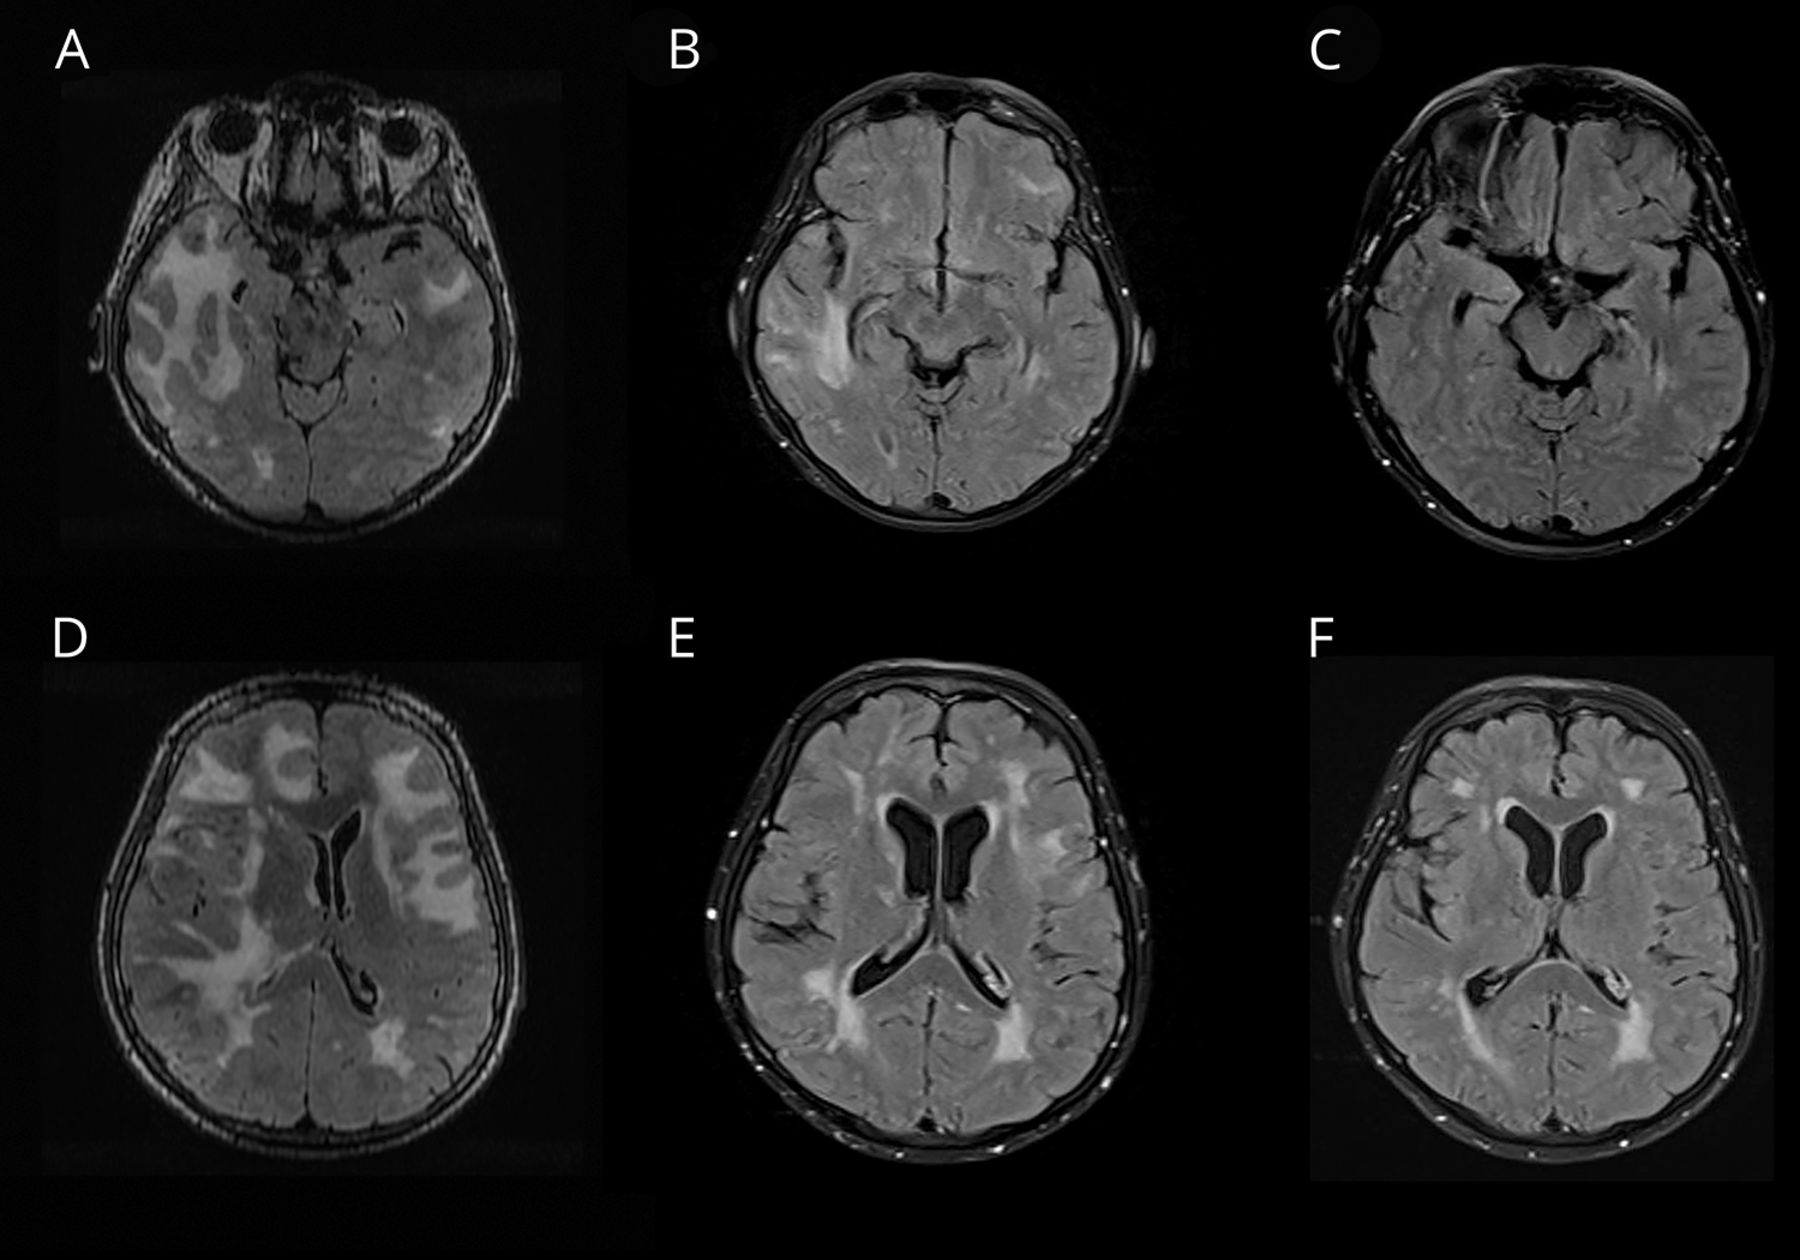

一个减轻以往健康的60岁的女人插管头痛和个月历史的帷幕,历史的记忆丧失。MRI进行(图1)。数字减影血管造影的头,水痘一带状疱疹病毒PCR,免疫球蛋白G CSF,肝炎B / C, CSF隐球菌抗原,艾滋病毒、莱姆血清学和梅毒屏幕是负的。最初的鉴别诊断包括中枢神经系统血管炎和颅内淋巴瘤。她被诊断出患有炎症基于clinicoradiologic标准脑淀粉样血管病(敏感性为82%,特异性为97%),1梗死认为amyloid-β-related脉管炎亚型。几天之内的类固醇,她完全清醒,重复MRI 5个月后显示改善脑白质病(图2)。蒙特利尔认知评估分数23/30开始后的两周治疗和22/30 5个月后。

图1

最初的核磁共振

(一)t2加权融合性的脑白质病扩展到皮层下白质质量效应。(B) Diffusion-weighted成像10天后变化对表观扩散系数序列相关(见图)与梗塞是相一致的。(C)梯度回波序列显示microhemorrhages。